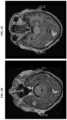

• FIG. 6A shows the number of CD3+/CAR+, CD4+/CAR+, CD8+/CAR+ T cells in peripheral blood of a subject with chemorefractory transformed DLBCL measured at certain time points.FIG. 6B depicts a pretreatment axial PET-CT image showing an intracranial abnormality in the right middle cranial foss and extensive abnormality in subcutaneous tissues in the right posterior auricular region.FIG. 6C is a post-treatment PET-CT image depicting resolution of the abnormality in FIG. 2B after treatment with anti-CD19 CAR+ T cells.FIG. 6D is a pretreatment brain MRI (high-resolution T1-weighted image with the use of contrast material; axial view) showing a homogeneously enhancing mass in the right middle cranial fossa.FIG. 6E is a post-treatment MRI image showing near-complete resolution of the enhancing mass.FIG. 6F is an axial PET-CT image at relapse showing right posterior auricular tumor recurrence associated with intense uptake of18F-flurodeoxyglycose (arrow).FIG. 6G is a PET-CT imaging showing resolution of the posterior auricular tumor after incisional biopsy and re-expansion of CAR+ T cells.